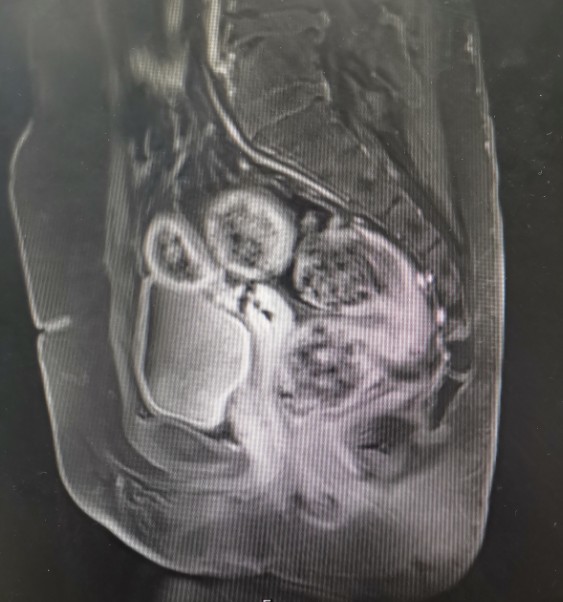

•全腹核磁:子宫术后改变,脂肪肝,双肾囊肿,盆腔少量积液。

矢状位T1

矢状位T2